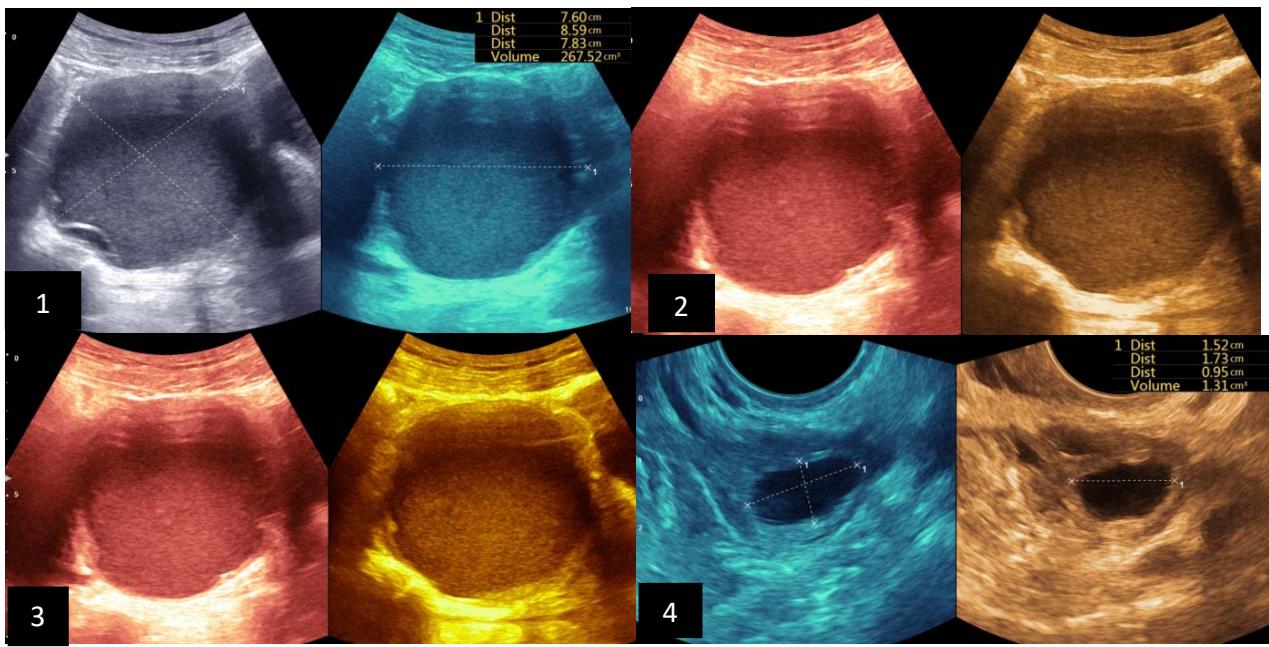

Tshibasu Tshienda et al. Percutaneous Radio-Guided Chemical Ablation with Absolute Ethanol of Cystic and Solid Lesions in Kinshasa Hospital Environments

Tshibasu Tshienda et al. Safety and Diagnostic Accuracy of Biopsy of Targeted Splenic Lesions Under Ultrasound Guidance Using the Multiple-Pass Technique Without Co-Axial in Kinshasa Hospitals